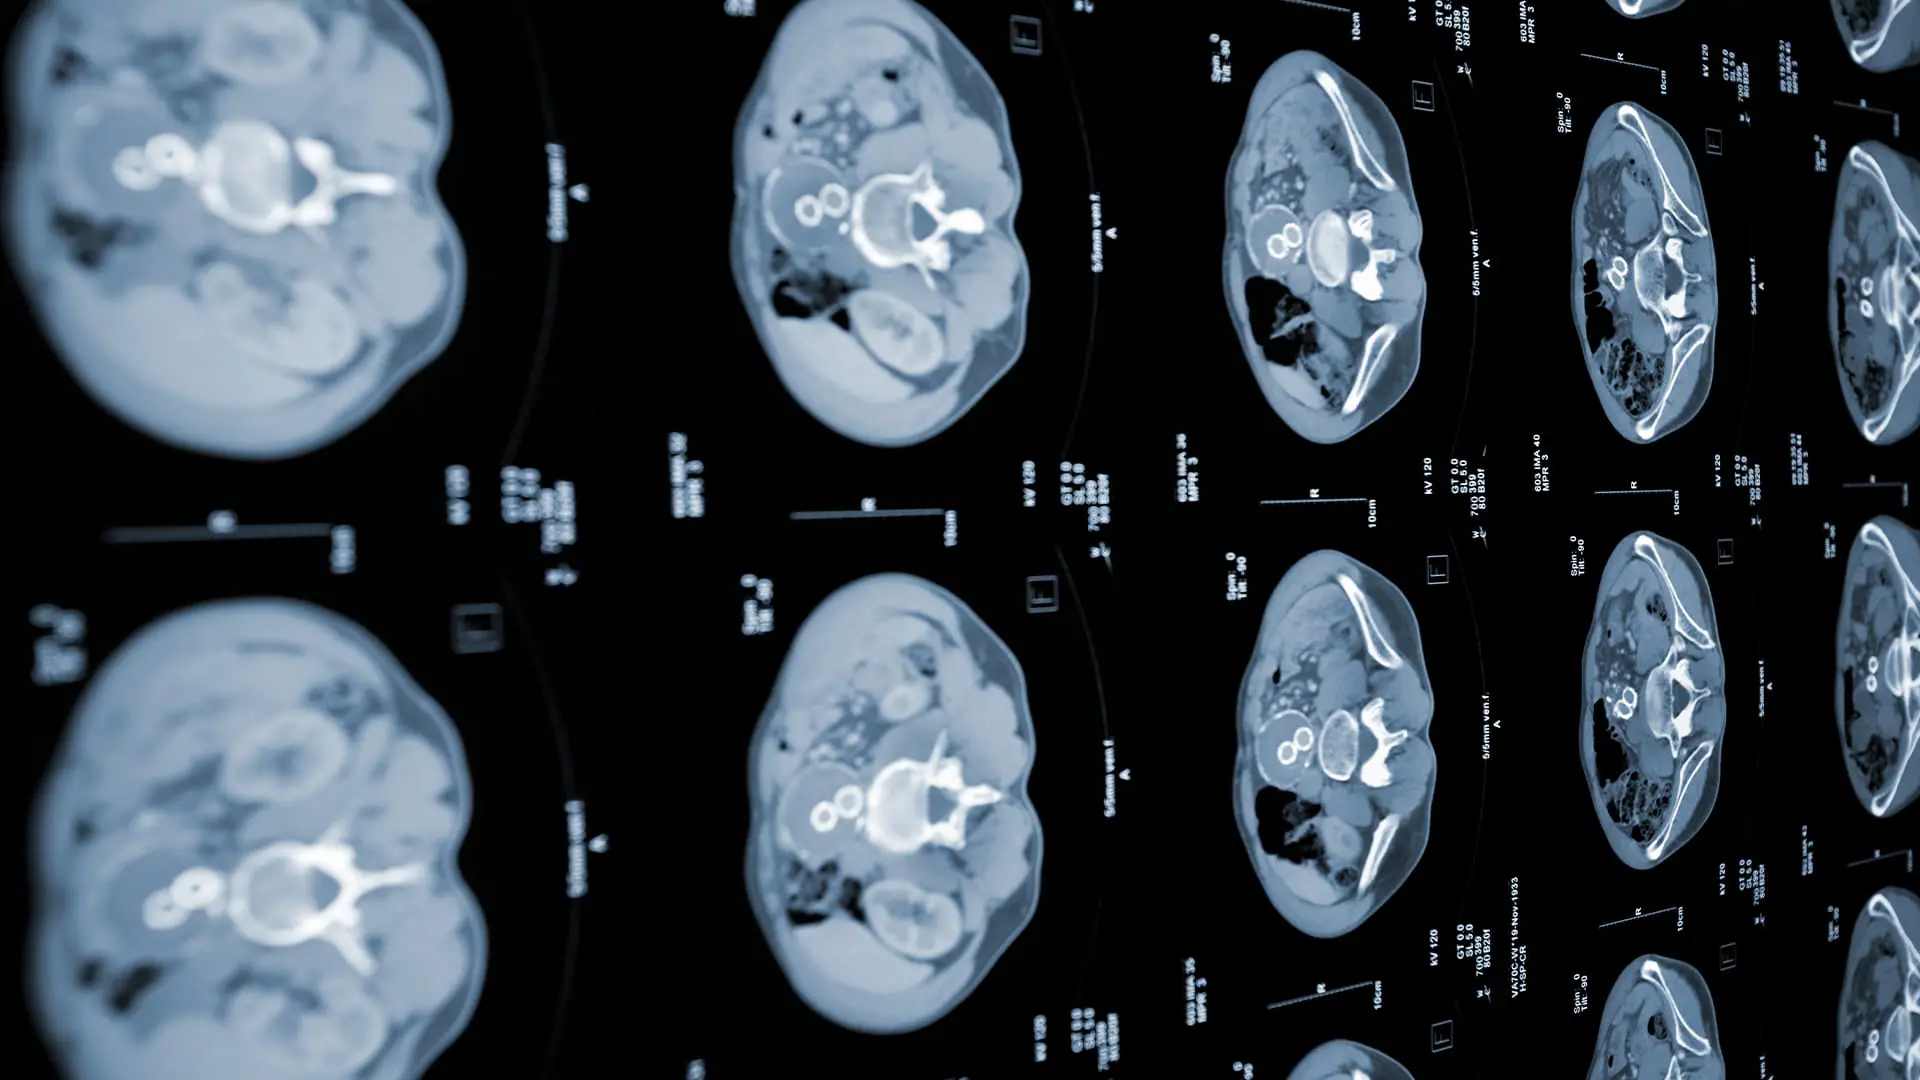

In a significant advancement for early cancer detection, researchers at the Massachusetts Institute of Technology (MIT) have developed two artificial intelligence (AI) models capable of identifying pancreatic cancer more effectively than current methods. Operating under MIT’s Computer Science and Artificial Intelligence Laboratory (CSAIL), these models form the PRISM neural network, focusing specifically on pancreatic ductal adenocarcinoma (PDAC), the most common type of pancreatic cancer.

The traditional methods of PDAC screening identify about 10 per cent of cases. However, PRISM has remarkably improved, successfully identifying PDAC in 35 per cent of cases. This leap in detection rates is a noteworthy achievement in medical diagnostics.